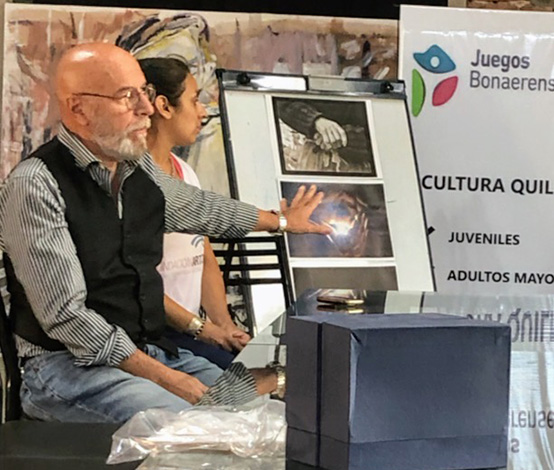

Se entregaron premios del concurso de fotografía “Las Manos y su Mundo” organizado por Fundación Articular y con el auspicio la Municipalidad de Quilmes, Cuatro Medios y el servicio de reumatología de Instituto Médico CER.

A partir de la expresión artística, considerando que las manos son la “tarjeta de presentación” de la artritis reumatoidea, el concurso propone generar conciencia social de su diagnóstico temprano. Las imágenes deberían ser de mano/s en sus distintas expresiones, con o sin enfermedad, solas o en una actividad siempre que se muestren como protagonistas de la obra.

- Primer premio: Susana Schwarcz. Obra “Con el correr del tiempo”

- Segundo premio: Carla Micaela Silva. Obra “En sus manos”

- Tercer premio: Gerardo Borgogelli. Obra “Con el pasar de los años

El Dr Velasco Zamora, presidente Fundación Articular, durante el evento concientizando acerca de la importancia del diagnóstico precóz de la artritis reumatoidea.